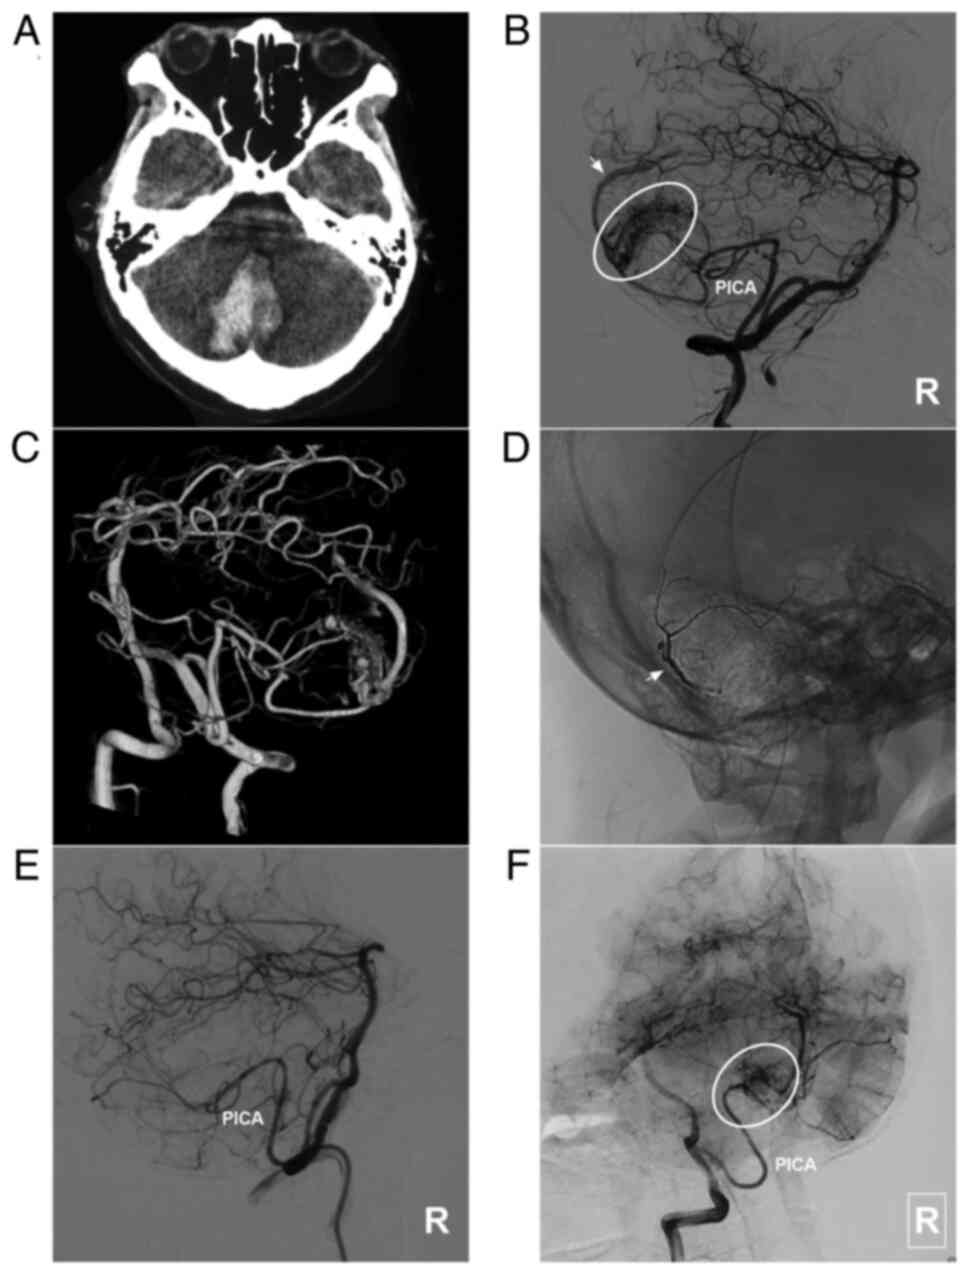

AVM located in the lower cerebellum supplied by the PICA alone. (A) Brain CT scan showing a cerebellar vermis hematoma. (B) Lateral DSA of the right vertebral artery in the arterial phase showing that the AVM was supplied by the PICA (ellipse), and the arrow indicates superficial vein drainage. (C) Three-dimensional DSA showing the AVM more clearly. (D) X-ray film showing the Onyx™ casting (arrow). (E) DSA in the arterial phase after EVT showing that the AVM is not visualized. (F) DSA at the 6-month follow-up indicates a small residual AVM (ellipse). The case presented in this figure was a 19-year-old female. She experienced sudden headaches, and she was awake after their onset. EVT was performed. No EVT complication was observed. The woman currently exhibits a normal health status. AVM, arteriovenous malformation; CT, computed tomography; DSA, digital subtraction angiography; PICA, posterior inferior cerebellar artery; R, right.

Figure 5

AVM combined with a prenidal aneurysm on the SCA. (A) Brain CT scan showing subarachnoid hemorrhage in the right ambient cistern. (B) Brain CTA showing the right SCA feeding the AVM (circle), and an aneurysm (arrow) is observed. (C) Two-dimensional and (D) three-dimensional DSA showing that the aneurysm (arrow) can be observed. (E) Unsubtracted DSA showing that the prenidal aneurysm was occluded with Onyx™ casting (arrow). (F) Following embolization, the aneurysm was not observed. The case presented in this figure was a 67-year-old male with a sudden headache; he was awake after its onset. Following EVT, conservative treatment was administered, and no EVT complications were observed. His health status is currently classified as normal. AVM, arteriovenous malformation; CT, computed tomography; CTA, computed tomography angiography; DSA, digital subtraction angiography; L, left; R, right; SCA, superior cerebellar artery.